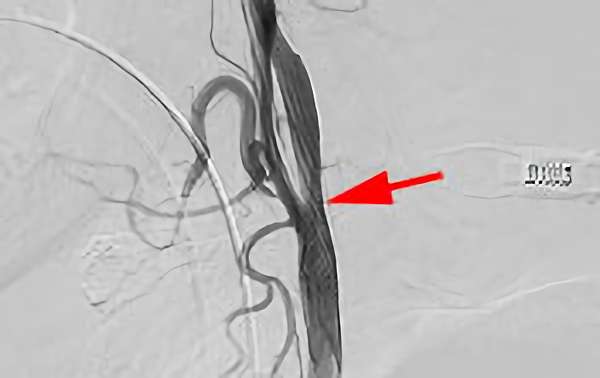

左内頚動脈狭窄症

No.892 手術前

No.892 手術中